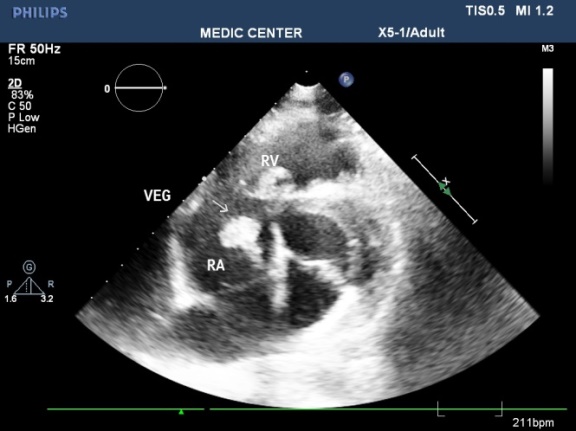

The vegetations in our study have been found on the mitral leaflets with MVP, bicuspid aortic cusps, pulmonary valves and beside small VSD [11-17].

Among 12 cases of Infective Endocarditis, the underlying cardiac lesions includes MVP, Bicuspid Aorta, VSD and pulmonic valve stenosis (Table 2) (Figures 44-51).

Figure 46. Vegetation seen at patient with VSD, 2DTEE imaging

Figure 47. Vegetation seen at patient with VSD, Live 3DTEE imaging